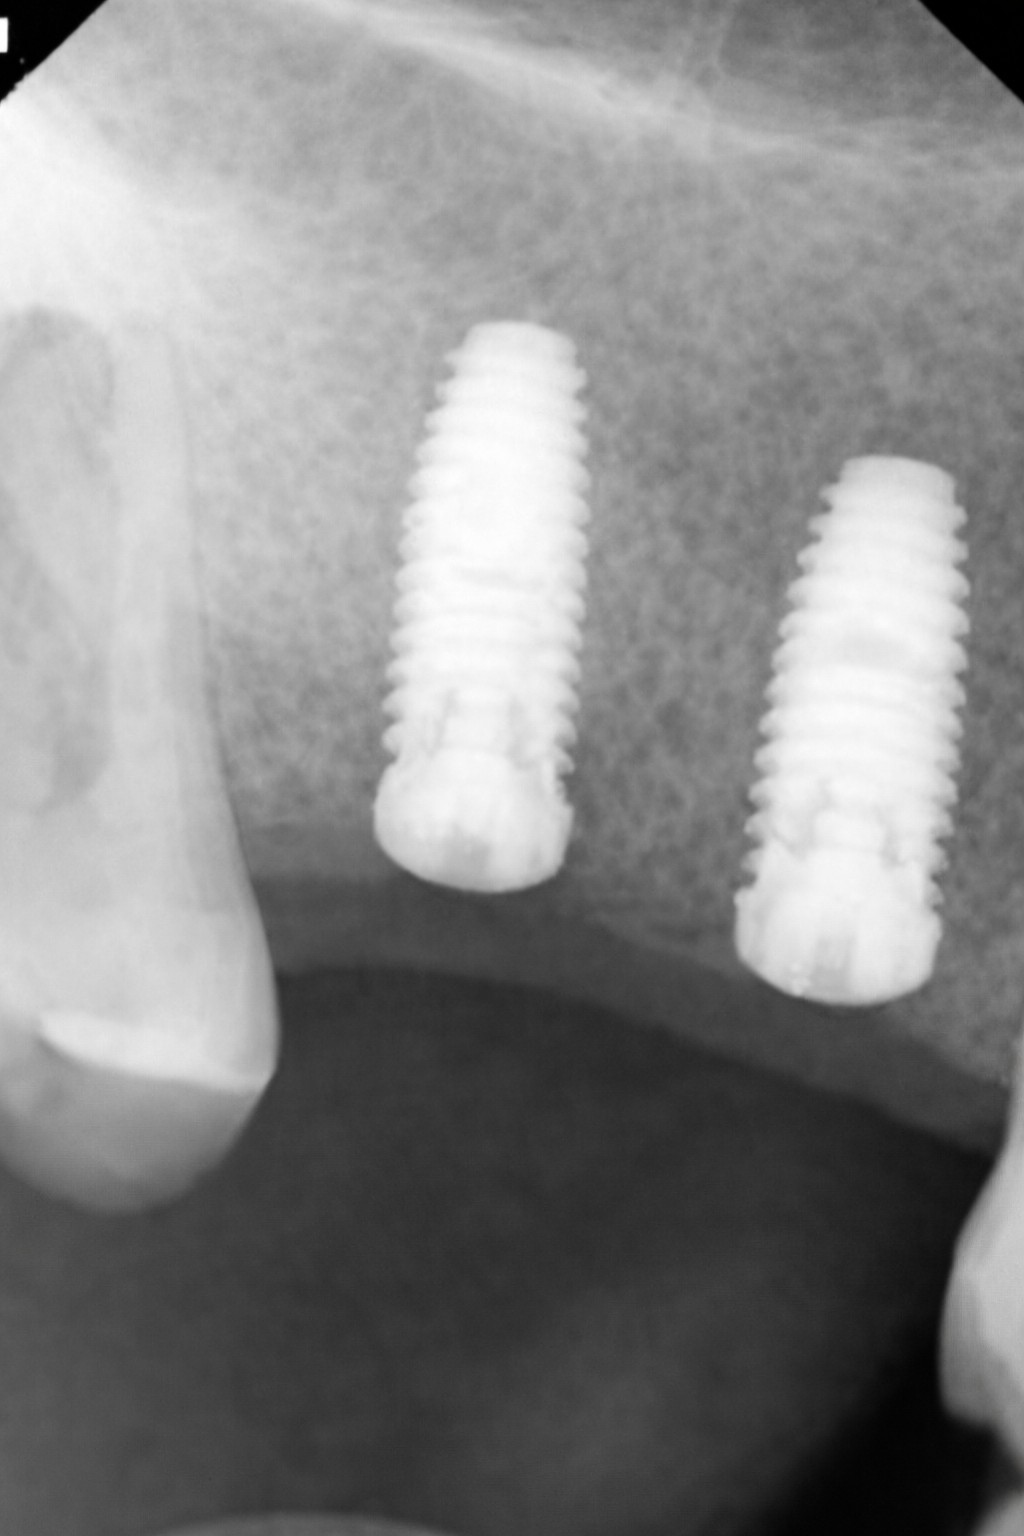

임플란트를 단순히 잇몸에 인공 나사를 심는 과정으로 생각하기 쉽습니다. 하지만 시술의 장기적인 성공을 결정짓는 핵심은 인공 치근이 자리 잡을 ‘토양’, 즉 치조골(잇몸뼈)의 양과 질입니다.

나무를 심을 때 흙이 얕으면 뿌리가 흔들리듯, 뼈가 부족한 상태에서 무리하게 임플란트를 심으면 수년 내에 보철물이 흔들리거나 빠지는 재수술로 이어집니다.

이때 시행하는 뼈이식(GBR, 골유도재생술)은 빈 공간을 단순히 채우는 것이 아닙니다. 뼈 이식재로 공간을 확보하고, 우리 몸이 스스로 튼튼한 새 뼈를 만들어내도록 유도하는 고도의 재생 의학 기술입니다.